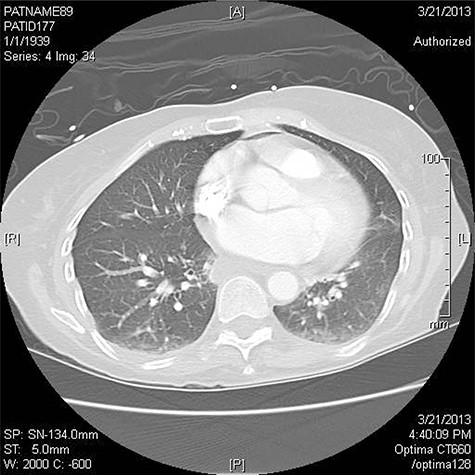

The incidence of this complication is between 0.03 and 1.5% [3]. The mortality following this complication ranges from 40 to 80% [3]. Surgical intervention is the recommended treatment, but successful intervention is limited. Clinical suspicion should remain high in patients status post ablative procedures who present with complaints including fever, hematemesis or neurologic symptoms [4]. The diagnostic tool of choice is computerized tomography (CT) scan of the chest [1, 3]. Surgical procedures noted in the literature include esophageal ligation and decompression, stenting of the esophagus and direct intracardiac or transthoracic repair with or without cardiopulmonary bypass (CPB; [5]). In this paper, we report successful repair via a novel surgical approach used in three patients.

Three patients have been treated by a single surgeon for left AEF. All presented with similar symptoms: chest pain, fever and dysphagia. The diagnosis was confirmed on CT scan of the chest (Fig. 1).

CT chest is the confirmatory test of choice [1, 3, 6, 8]. Findings include pericardial effusion, intravascular air, communication between the atrium and the pericardium or esophagus, and extensive systemic emboli [3]. Pneumomediastinum is a strong indicator of esophageal injury [1]. For patients who have neurologic symptoms a CT head is recommended [1].